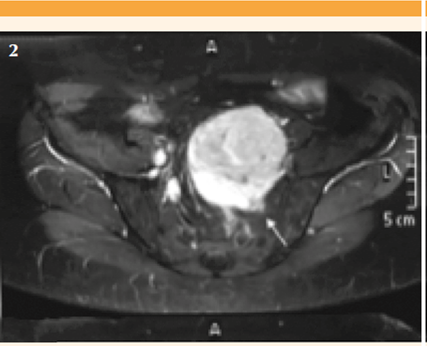

En la exploración laparoscópica el útero y los anexos se observaron normales y se apreció una gran masa retroperitoneal de 9 cm, adherida al sacro pero sin conexión con el útero. Ante estos hallazgos se suspendió el procedimiento programado y se le practicaron estudios complementarios. En la resonancia magnética nuclear contrastada de pelvis se encontró una masa retroperitoneal de 5.7 x 7.8 x 8 cm sugerente de tumor mesenquimal. Figuras 2 y 3

Figuras 2-3 Resonancia magnética del abdomen y la pelvis. Izquierda: axial T1 con supresión grasa, donde se observa la relación con el foramen neural S2 izquierda. Derecha: lesión extraperitoneal, encapsulada, heterogénea, sólida de 7x8 cm, anterior al sacro y superior al fundus uterino.